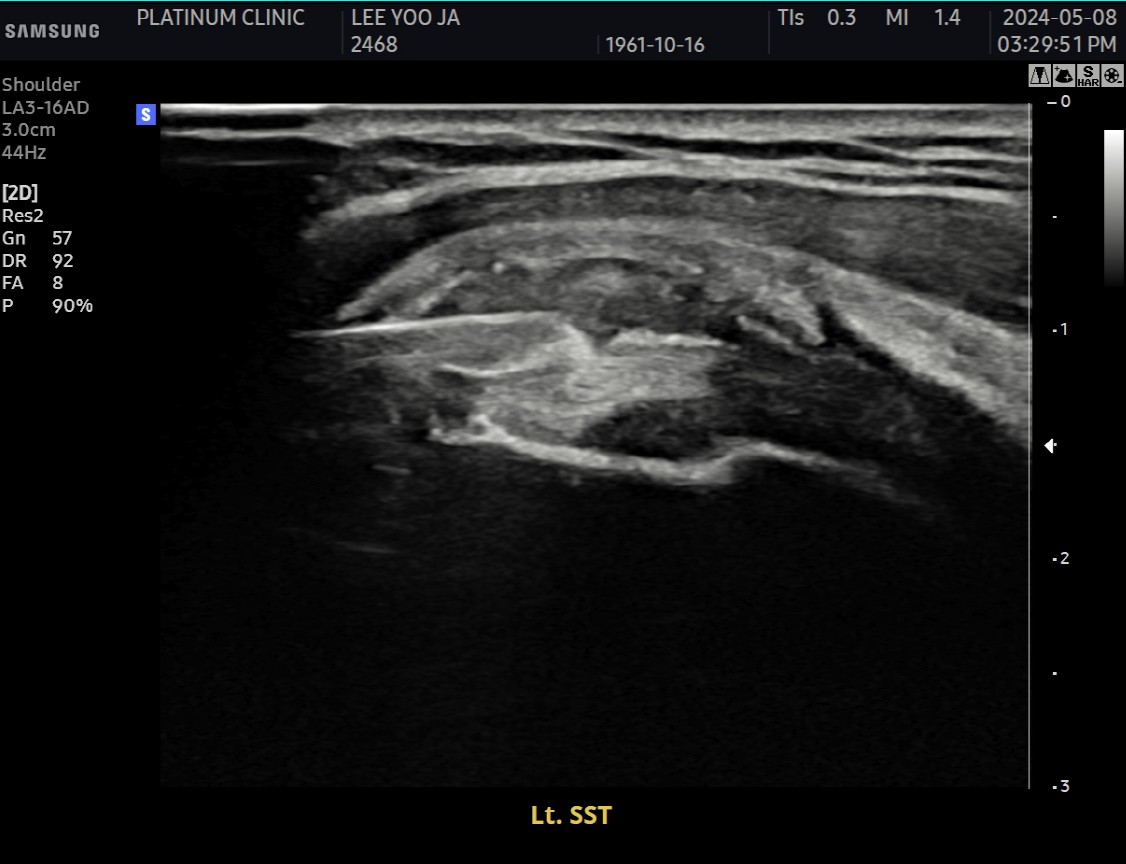

회전근개 힘줄 사이사이에 미세한 석회 침착이 여러 군데 흩어져 있었습니다. 크기가 매우 작아서 3mm 단위로 단면을 촬영하는 MRI에서는 보이지 않았지만, 초음파로는 선명하게 확인되었습니다.

2) 근본적인 문제 해결: 석회분쇄흡입술

근본 원인인 석회를 제거했습니다. 초음파로 확인된 미세석회들을, 석회분쇄흡입술을 통해 힘줄 사이사이에서 씻어내듯 제거했습니다.